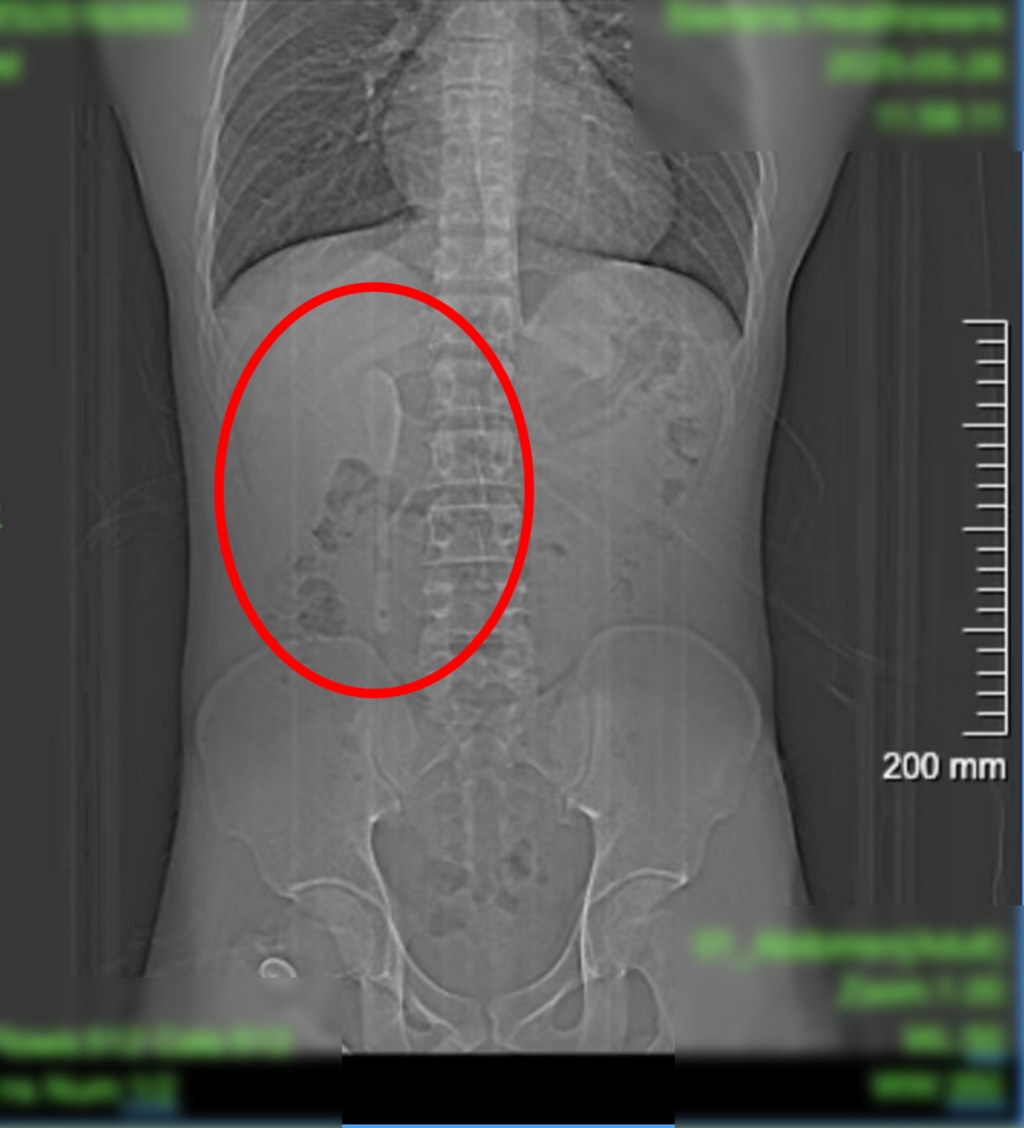

Các bác sĩ đã tiến hành khám sức khỏe và chụp CT để tìm nguyên nhân. Lúc đầu, bệnh nhân nghĩ rằng mình đã vô tình nuốt phải một vật bằng nhựa. Tuy nhiên, những gì họ tìm thấy là một chiếc thìa gốm dài 15 cm mắc kẹt trong tá tràng.

Bác sĩ Chu Bình Hồng, giám đốc trung tâm nội soi Bệnh viện Trung Sơn cho biết, thìa có bề mặt nhẵn và mỏng. Chiếc thìa bị kẹt ở chỗ nối giữa phần mở rộng của ruột non và thực quản, đây là một khu vực rất hẹp. Nếu không nhanh chóng lấy ra, có thể gây thủng ruột hoặc chảy máu trong nghiêm trọng.

Tuy nhiên, sau ca phẫu thuật nội soi kéo dài 90 phút, các bác sĩ đã có thể lấy chiếc thìa ra thành công mà không cần mở bụng. Tiêu Viêm không mất nhiều thời gian hồi phục và có thể trở về nhà sau vài ngày.